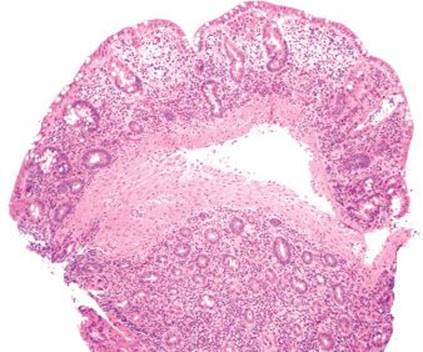

Figure 4.271 Endometriosis. This consultation case originated from a 25-year-old woman with a bleeding rectal mass. It was clinically ominous appearing, leading the surgeon to inform the patient that the lesion was most likely malignant. Based on the patient’s young age, the family asked for the case to be externally reviewed.

Figure 4.272 Endometriosis. Higher power shows convoluted glands surrounded by a cuff of stroma cells and intermixed lymphoid cells.

Endometriosis is the presence of at least two of the three following features outside of the uterus: endometrial glands, stroma, and hemorrhage (Figs. 4.271–4.273). Up to 37% of women with endometriosis have intestinal involvement, and any layer of the bowel can be involved. The clinicopathologic presentation is diverse and presentations can overlap with appendicitis, IBD, diverticular disease, infectious colitis, a surgical acute abdomen, malignancy.125–128 Endometriosis involving the rectum commonly presents as bloody diarrhea. Associated pathologic findings can include strictures, ulceration, fissures, ischemia, and intussusception.125 The lesions can appear as polyps or bleeding mass lesions, raising clinical concerns for malignancy. The overlying colonic epithelium can be markedly reactive and mimic dysplasia, leading to the misdiagnosis of colonic adenocarcinoma. Occasionally, only the stromal component is seen and a diagnosis of sarcoma is entertained. In these cases, usually the endometrial glands can be identified on deeper sections. Confirmatory immunohistochemical stains include ER and PR to highlight the glandular components and CD10 to highlight the endometrial stroma.